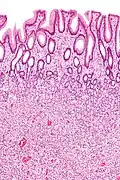

| Hyperplastic polyp of the stomach | Stomach | Elongated, tortuous, and cystic foveolae separated by edematous and inflamed stroma.[14] | ![]() |

Gastric hyperplastic polyposis | |